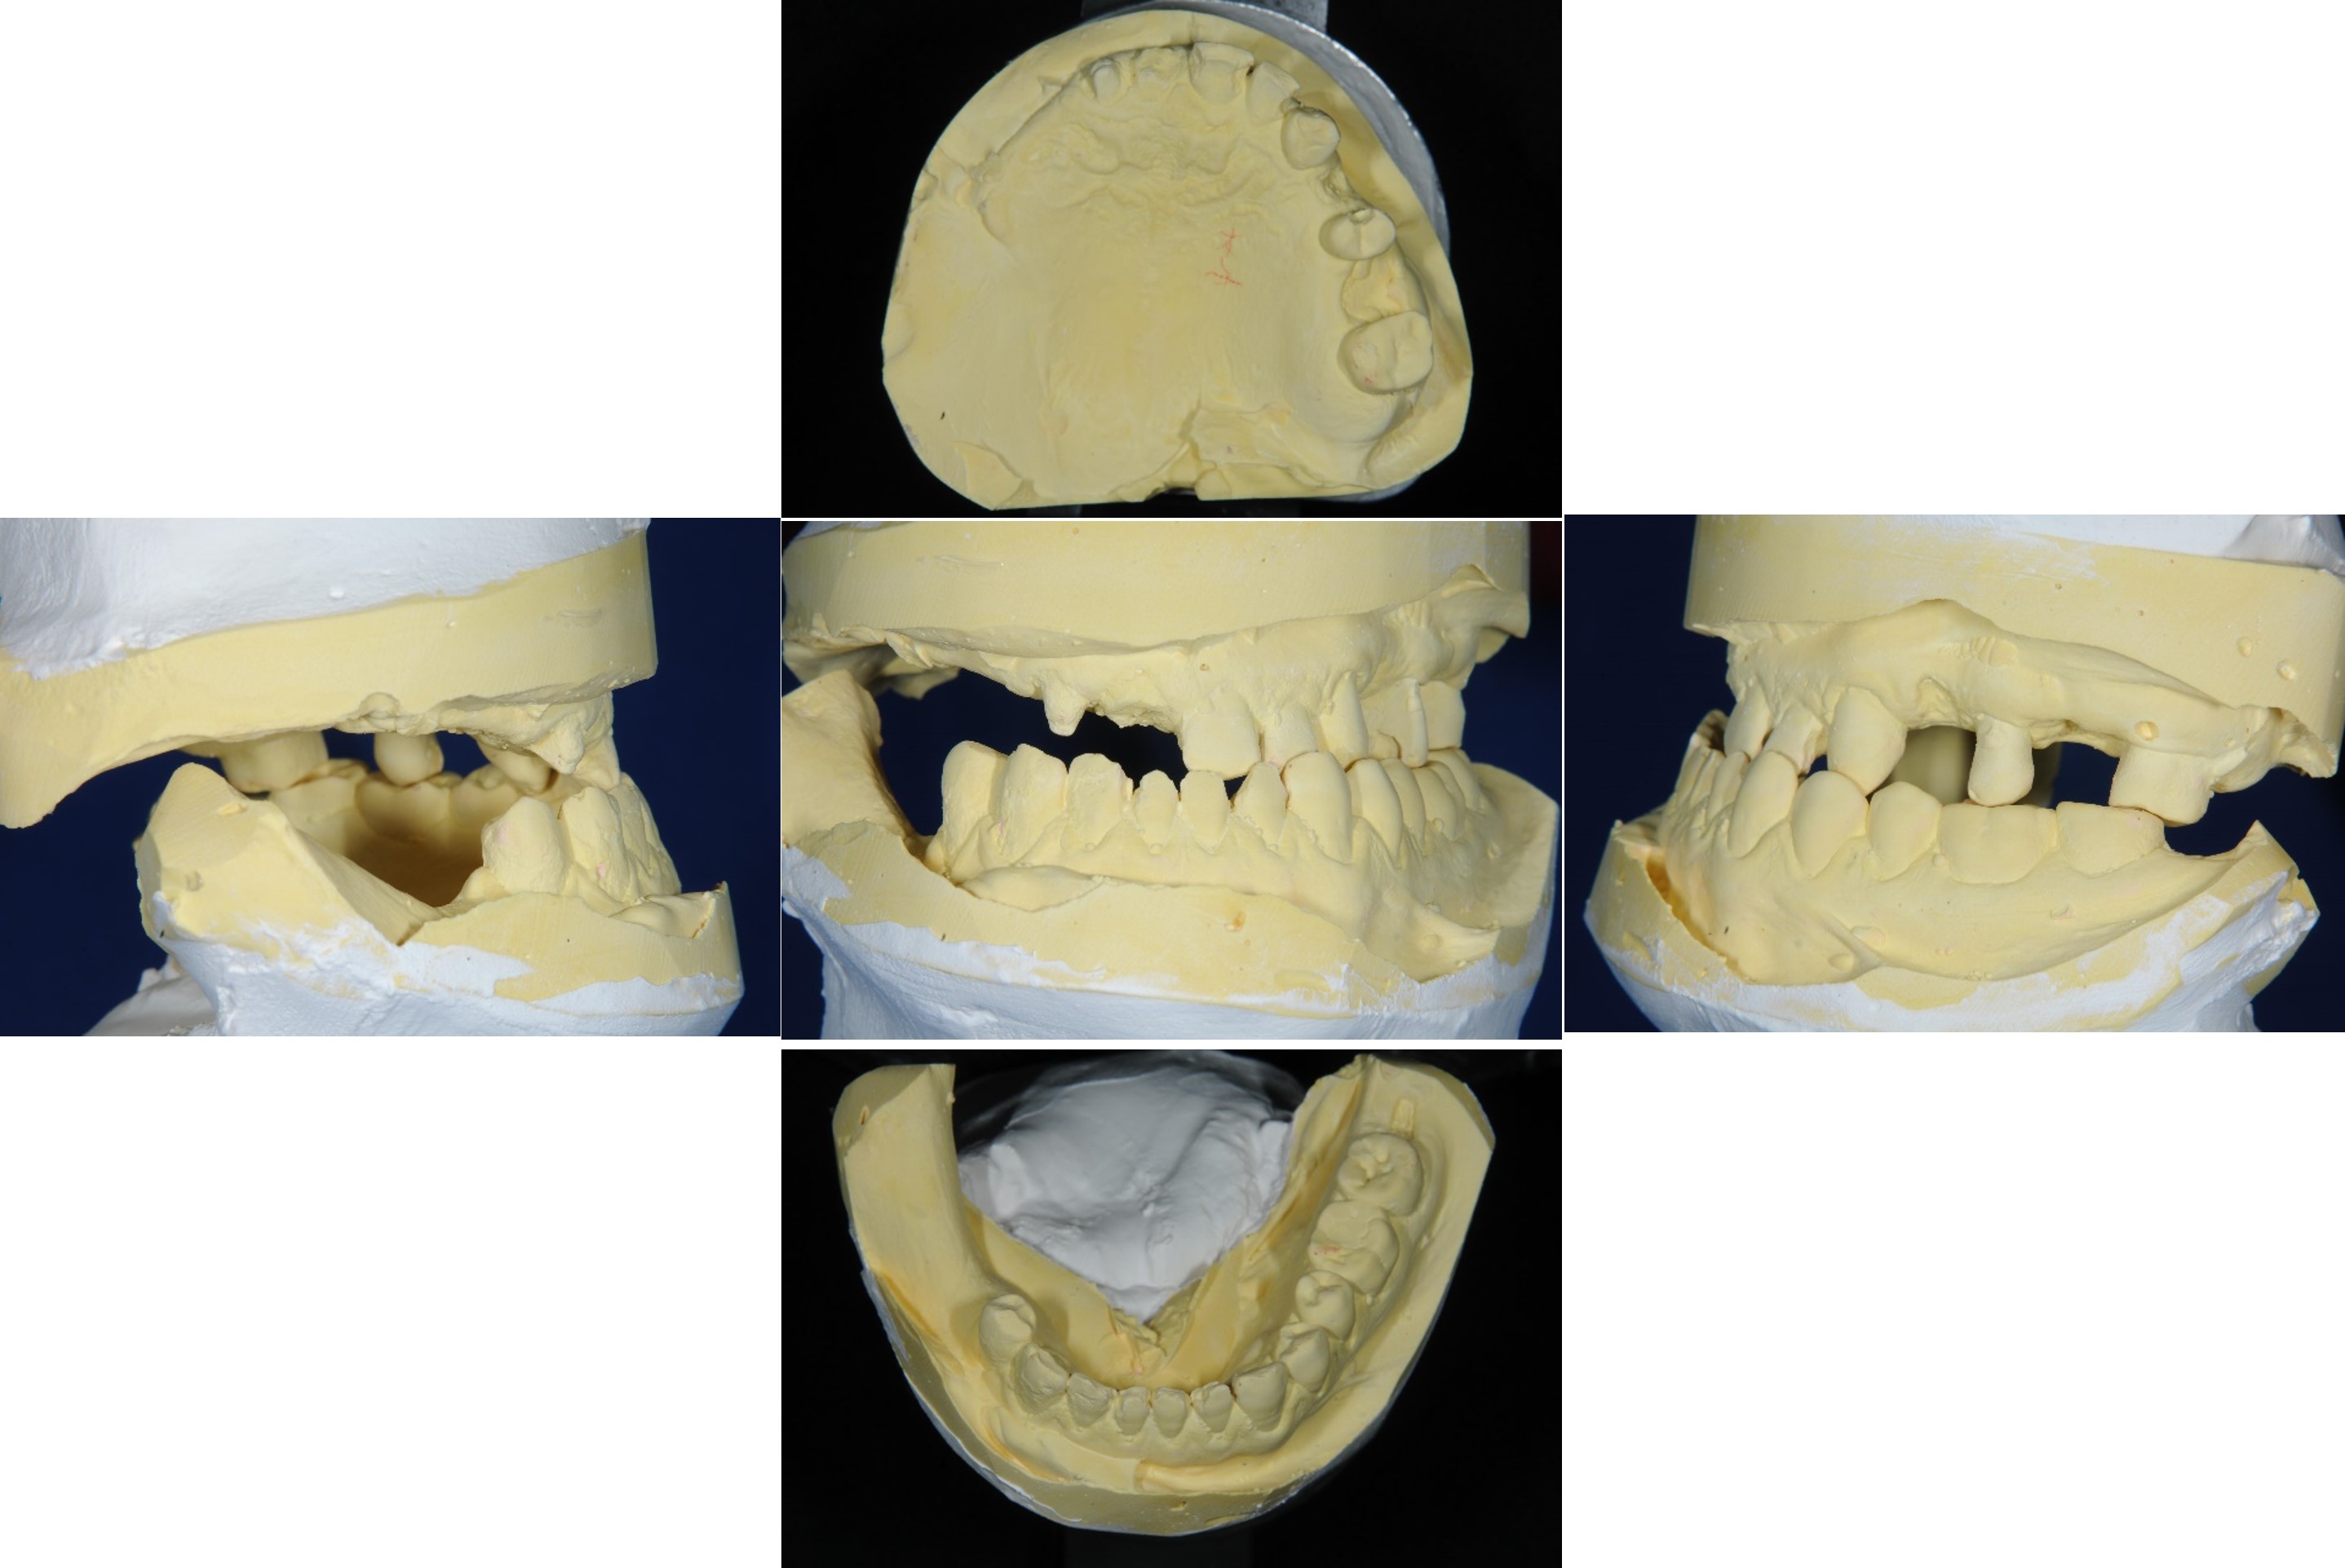

上下顎初步印模

模型咬合分析